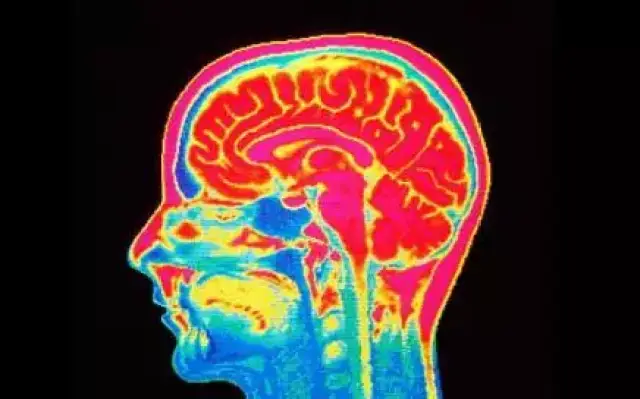

倒是有研究显示,恋童癖患者的大脑结构与众不同,并且有些身体性状也和常人有异。位于多伦多的加拿大成瘾和精神健康中心(CAMH)的詹姆斯·康托和他的同事们发布的结果显示,恋童癖患者大脑中的白质少于常人。